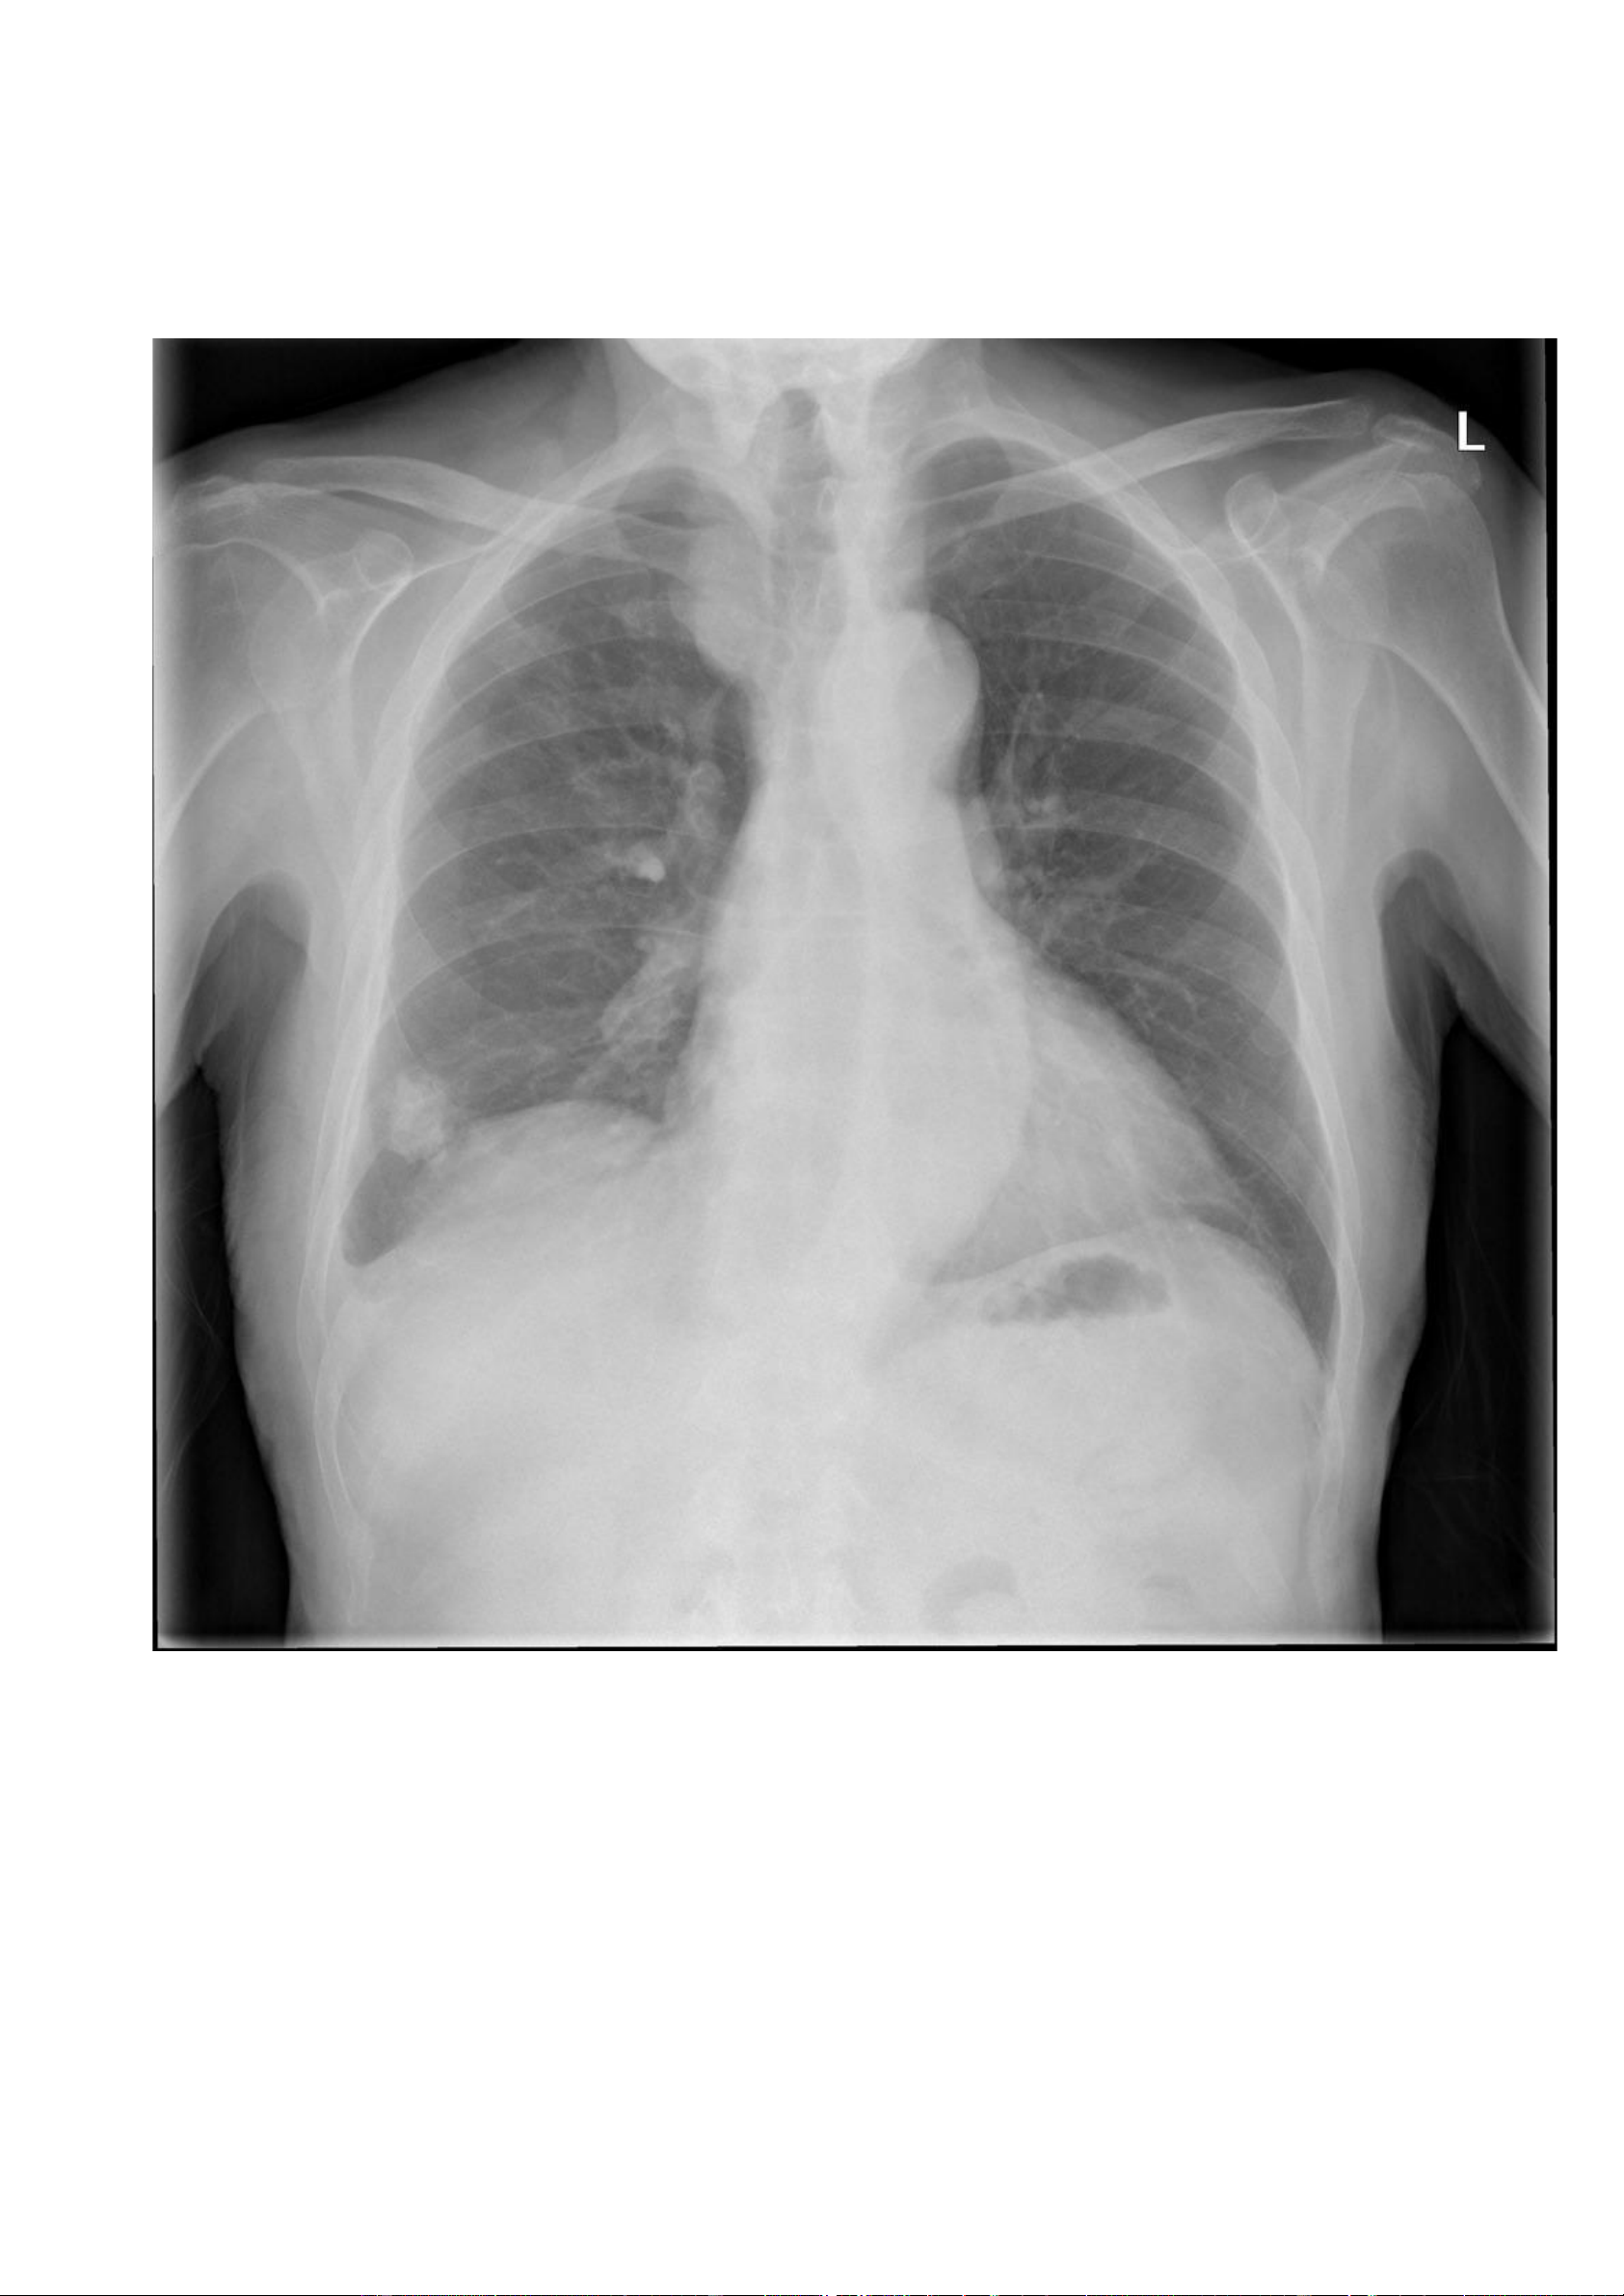

Nguồ https://radiopaedia.org/cases/pleural-plaques -

nh nhân: Bệnh nhân nam, 65 tuổi, khó thở và ho có đờm. - Hình ả lOMoAR cPSD| 22014077 Phan Tùng Bách

Vôi hoá màng phổi hai bên dạng bản đồ, bao gồm cả bề mặt nửa cơ hoành hai bên. lOMoAR cPSD| 22014077 Phan Tùng Bách ờng hợ n link: Thông tin bệ nh X quang:

Các mảng màng phổi vôi hoá (các đường nét đứt màu vàng). 7.5. Trư p 5: lOMoAR cPSD| 22014077 Phan Tùng Bách -